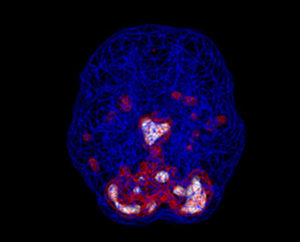

Estudos de imagens cerebrais mostram que a depressão não é uma falha de carácter ou fraqueza pessoal. Está

associado a mudanças biológicas no cérebro. Pessoas com depressão geralmente têm muita atividade no sistema límbico profundo – os centros emocionais do cérebro. Mas nem todos com depressão têm os mesmos padrões cerebrais subjacentes. Nas nossas investigações, a imagem cerebral mostrou-nos que existem 7 padrões cerebrais diferentes associados à depressão, e conhecer o seu tipo pode ser a chave para obter o tratamento mais eficaz

SPECT (tomografia computadorizada por emissão de fóton único) é um estudo de medicina nuclear que avalia o fluxo sanguíneo e a atividade no cérebro.

Basicamente, ele mostra três coisas: atividade saudável, pouca atividade ou muita atividade. Uma varredura “ativa” saudável mostra as partes mais ativas do cérebro com azul representando a atividade média e vermelho (ou às vezes vermelho e branco) representando as partes mais ativas do cérebro. No exame saudável à esquerda, a área mais ativa está no cerebelo, na parte posterior/inferior do cérebro. A imagem do cérebro à direita mostra hiperatividade no sistema límbico profundo (o centro emocional do cérebro), um padrão comumente visto na depressão.https://www.youtube.com/watch?v=KZtYA–Yvjs